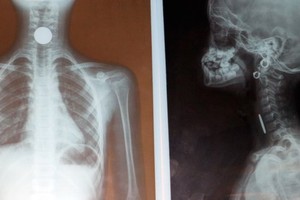

成功為女童取出食道內硬幣

醫生成功為女童取出硬幣